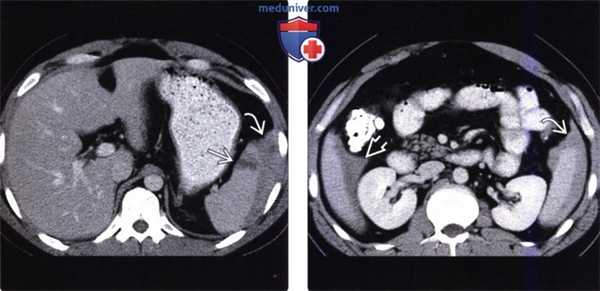

(Слева) На аксиальной КТ с контрастным усилением у женщины 39 лет, получившей множественные травмы в ДТП, в селезенке определяются многочисленные участки вытянутой и неправильной формы, не накапливающие контраст.

(Справа) На аксиальной КТ с контрастом у этой же пациентки (типичный случай разрыва селезенки) также определяются участки пониженного накопления контраста в селезенке, визуализируется небольшая гематома возле ее края.

(Слева) На аксиальной КТ с контрастным усилением определяется глубокий разрыв селезенки и активная экстравазация. Обратите внимание на разрыв нижнего полюса селезенки, где обнаруживается участок высокой плотности, свидетельствующий об артериальной экстравазации.

(Справа) На аксиальной КТ с контрастом у этой же пациентки определяется большая гематома около селезенки, а также признаки интенсивной артериальной экстравазации.

(Слева) На аксиальной КТ с контрастным усилением у молодого мужчины, пострадавшего в ДТП, определяется разрыв паренхимы селезенки с наличием сгустка крови высокой плотности, прилежащего к ее краю.

(Справа) На аксиальной КТ с контрастным усилением у этого же пациента также определяется сгусток крови, прилежащий к краю селезенки (типичный «сторожевой сгусток»), наряду со скоплением геморрагической жидкости меньшей плотности, более однородной структуры, во всех отделах брюшной полости. Заживление произошло самостоятельно, без хирургического вмешательства.